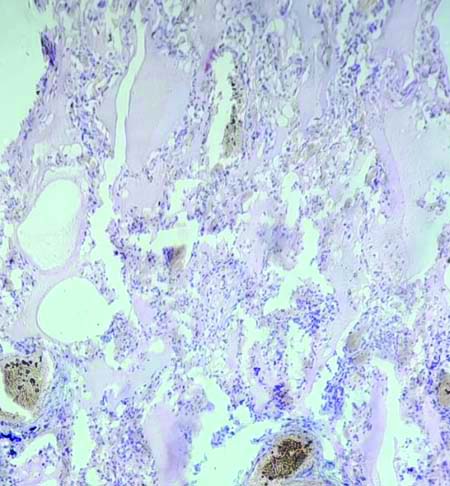

The lungs typically showed congestion grossly in most of the specimens, with some exhibiting heavy congestion and frothy secretion upon dissection. Under the microscope, notable findings in the lungs included diffuse alveolar haemorrhage [Table/Fig-13], emphysema [Table/Fig-14], pulmonary oedema [Table/Fig-15], and chronic venous congestion.

Histopathological picture from lung shows diffuse alveolar haemorrhage (H&E; X10).